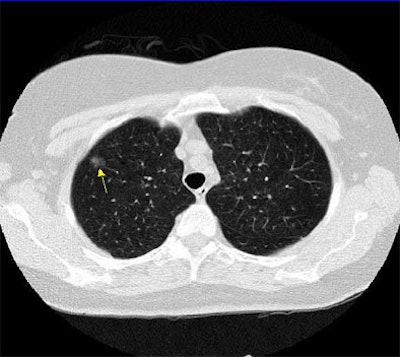

The differences go beyond semantics -- the findings speak volumes about the prognostic implications of the abnormalities, Yankelevitz said. Part-solid nodules in particular have a very high frequency of malignancy, he said, even more than do solid or non-solid lesions.

"These part-solid nodules can have linear extensions extending from them, in fact, very consistently. Pathologically they've been shown to correlate with extension of the lymphatic system," he said. "And you can also see this pattern (in) dilated bronchi within these part-solid lesions. It's interesting when you biopsy these, you often get fibrotic material that comes out; you have to be very careful. These tend to be in areas of fibrosis that perhaps causes the dilatation of these bronchi."

![]() |

| Part-solid nodule with linear extensions. All images courtesy of Dr. David Yankelevitz. |